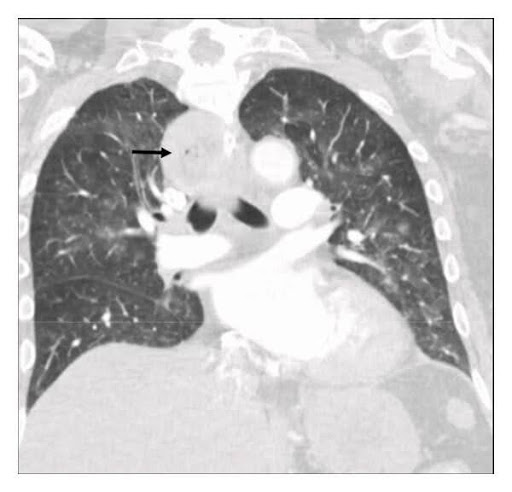

Durch die anschließend durchgeführte Laryngoskopie konnten die Symptome nicht geklärt werden. Mit dieser Untersuchungsmethode ließen sich keine Anomalien darstellen. Mittels der dann durchgeführten Thorax-CT konnte eine Lungenembolie ausgeschlossen werden.1

Abb. 2: CT Thorax1

Hier zeigte sich eine fast vollständige Atelektase des linken Unterlappens und ein aufgeblähter Ösophagus. Der nächste Schritt umfasste eine Magenspiegelung, um der Sache auf den Grund zu gehen.